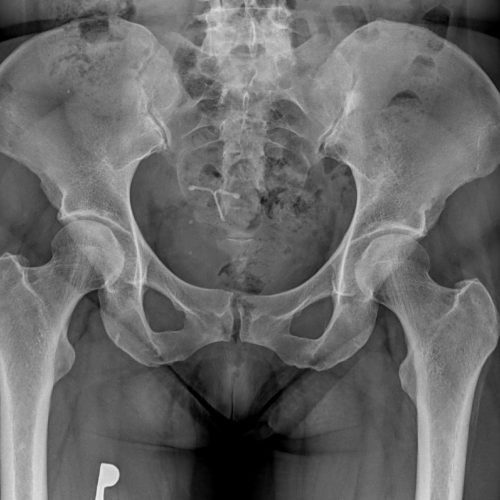

Zdaleka nejčastější příčinou bolesti kloubu je artróza. Ta začíná v chrupavce, která postupně ztrácí pevnost a pružnost. Ztenčuje se až může zcela zaniknout. Chrupavka v kloubu funguje jako nárazník mezi kostmi. Tlumí tedy nárazy a snižuje tření mezi kloubními plochami. Při úbytku kloubní chrupavky trpí všechny přilehlé kloubní struktury. Pod chrupavkou jsou kosti, jejichž obnažování způsobuje bolesti. Doprovodem bývá nestabilita kloubu, kostní nárůstky a deformace.